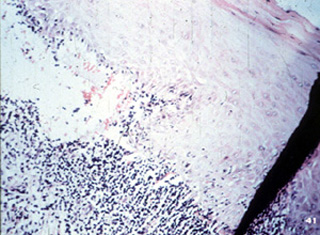

| El liquen

plano erosivo, sin embargo, la degeneración de la basal procede a un punto dónde el epitelio se separa del tejido conjuntivo subyacente. Note en esta vista a

una mayor resolución que las células basales ya no se atan al epitelio

o al tejido conjuntivo subyacente. Esto produce descamación clínica y

ulceración. Uno no esperaría ver vesículas intactas o ampollas.